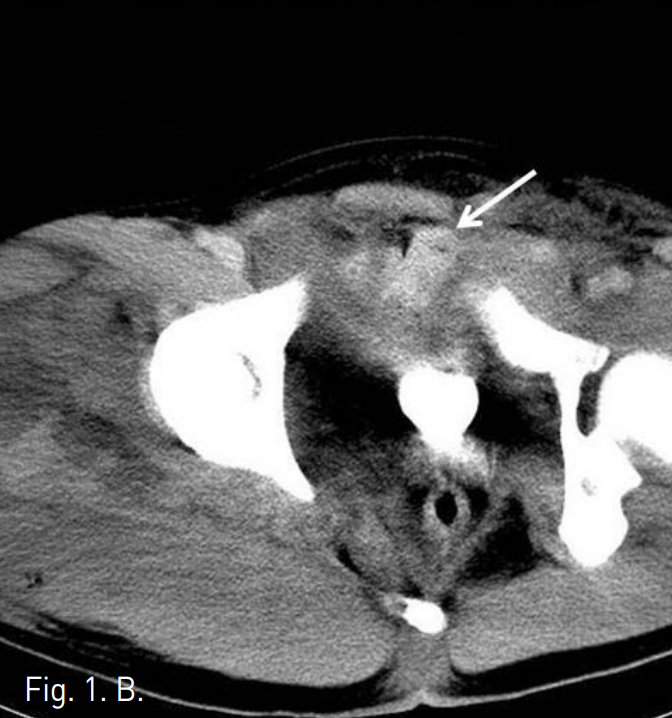

Emergency abdominal CT was performed to evaluate bleeding focus. Cystogram and abdominal CT revealed an extraperitoneal hematoma of the suprapubic area and marked widening of symphysis pubis(Fig 1). The CT findings were highly suggestive of inferior epigastric and obturator arterial injury. Enhanced study showed an extravasation within the mass indicative of arterial bleeding.

Fig 1.

A. Cystogram shows an external compression of the bladder, suggestive of perivesical hematoma, associated with diastatic fracture of the symphysis pubis.

B. Pelvic CT shows a hematoma with extravasation of contrast in pubic area (arrow), indicating active hemorrhage.